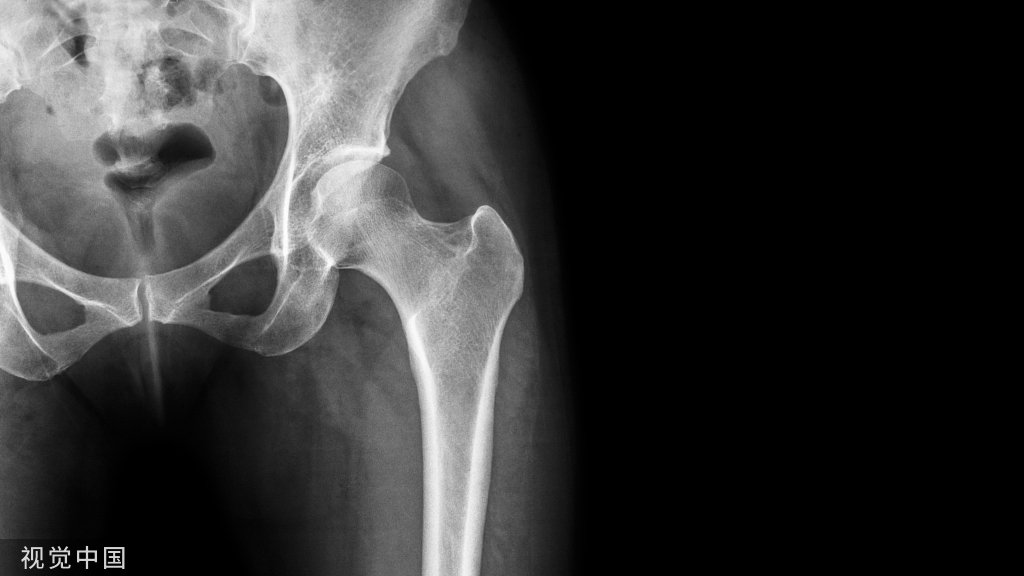

髋关节、骨盆以及腰部动得太多容易导致下背痛,可能是由于软组织不稳定造成过度的旋转或者前后左右移动。

下背的稳定来自于几条不同的肌肉以及韧带合力,让动态的力量可以锁定骨盆以及骨盆和髋关节。

很多的腰痛仔细检查会发现是臀大肌的痛点较多,且两侧臀大肌合力会让骨盆变成封闭的组织,因此骨盆的动作会受到影响。在生物力学上骨盆的疼痛可能会是单边的,甚至可能延伸到臀部以及大腿前面以及后面,最远会影响到小腿的外上侧,这些部分都与臀大肌的起点与终点不谋而合。